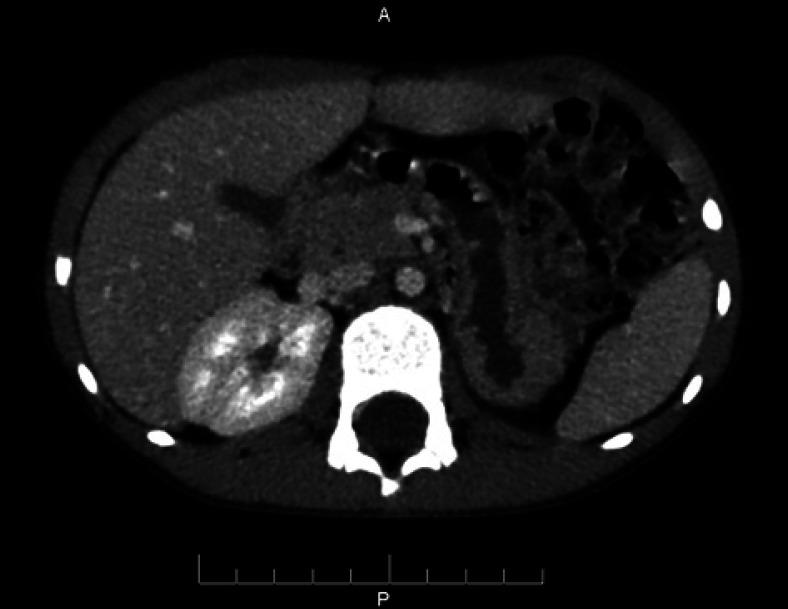

马蹄肾中的肾母细胞瘤

Wilms' Tumor in Horseshoe Kidney.

Wilms' tumor is the most common malignant kidney tumor found in children. The Horseshoe kidney is the most common renal fusion malformation. However, Wilms' tumor is rarely identified in horseshoe kidney patients. Multimodal treatments in Wilms' tumor can play important roles in increasing the survival rate. In this study, we report the case of a 6-year-old boy in whom a Wilms' tumor was identified in a horseshoe kidney. The tumor was successfully treated with preoperative chemotherapy, followed by surgical resection.

摘要

肾母细胞瘤是儿童中最常见的恶性肾肿瘤。马蹄肾是最常见的肾脏融合畸形。然而,马蹄肾患者中很少发现肾母细胞瘤。肾母细胞瘤的多模式治疗在提高生存率方面可发挥重要作用。在本研究中,我们报告了一名6岁男孩的病例,其马蹄肾中发现了肾母细胞瘤。该肿瘤通过术前化疗成功治疗,随后进行了手术切除。